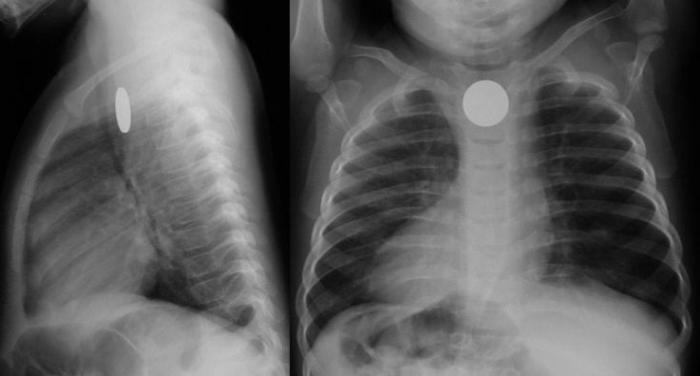

L'étude la plus simple et la plus efficace est une radiographie, avec laquelle vous pouvez déterminer l'emplacement d'un corps étranger. Tous les objets peuvent ne pas être visibles, par conséquent, vous devrez peut-être effectuer en plus une échographie ou un examen endoscopique. Les enfants sont généralement laissés à l'hôpital pendant 2-3 jours pour surveiller l'état ou décider si une intervention supplémentaire est nécessaire. Si l'article est petit et ne constitue pas une menace pour la santé, l'enfant est en paix et à chaque selle, il vérifie si le corps étranger est parti.